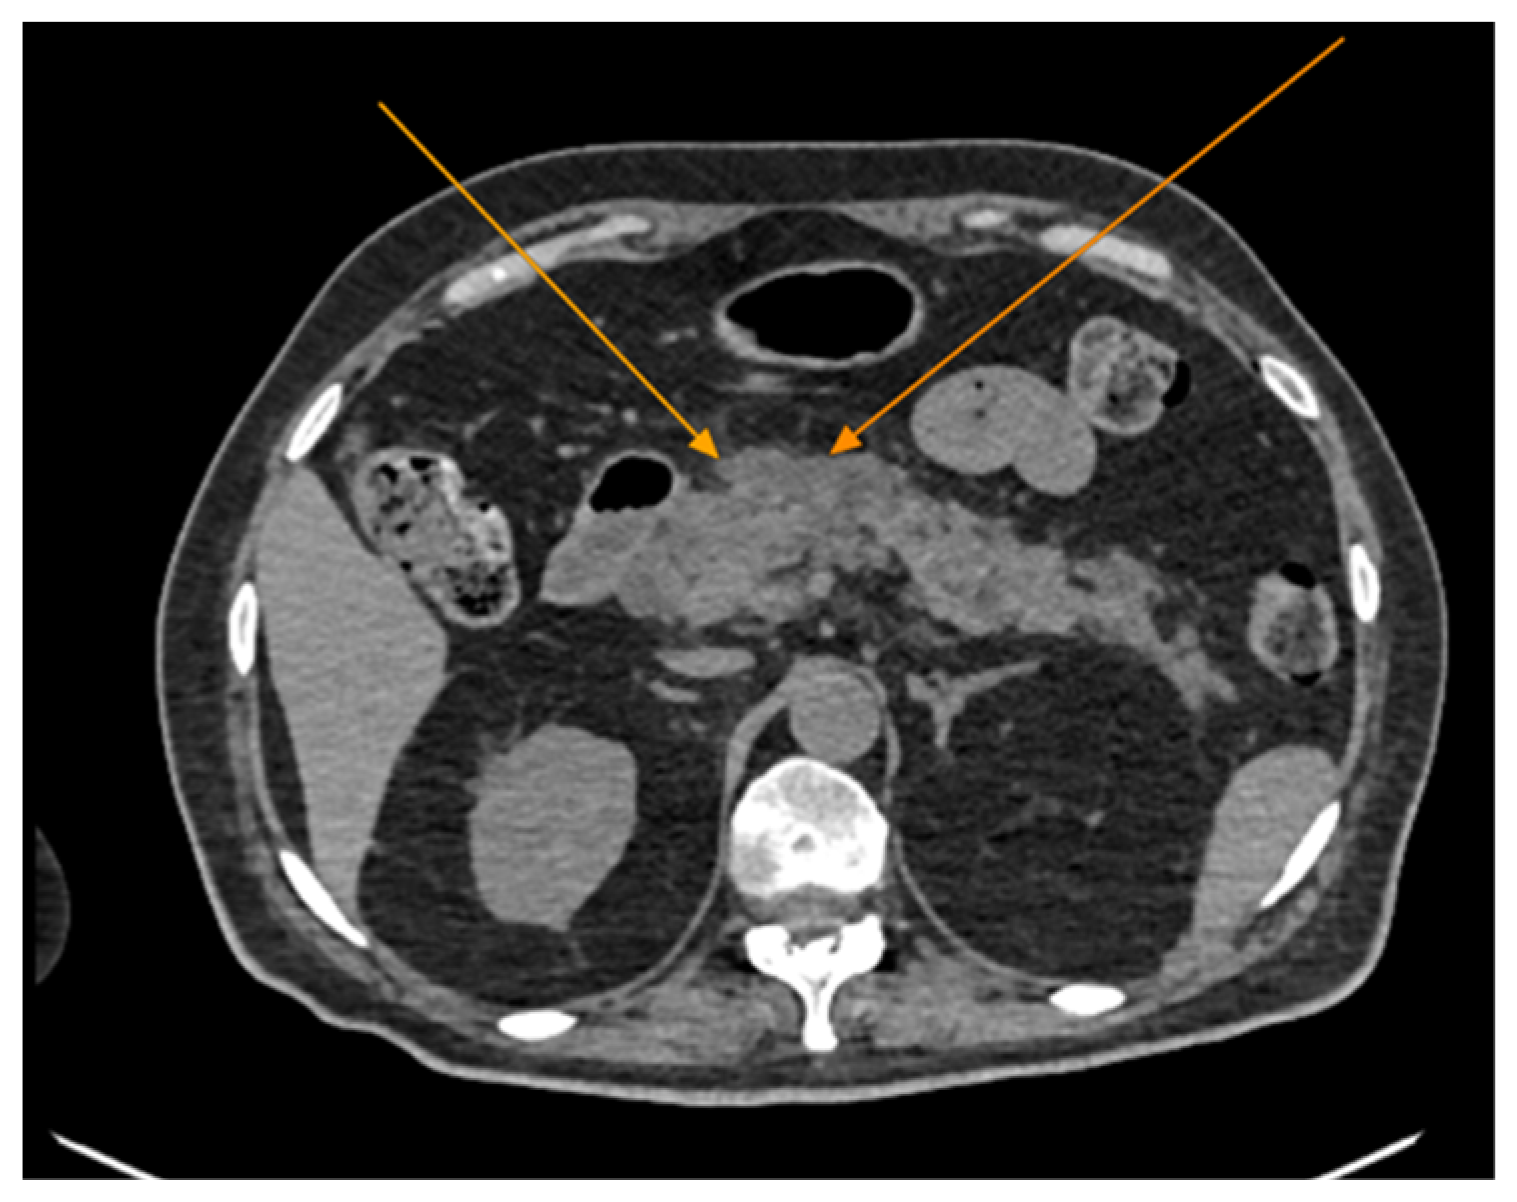

The patient was referred to diabetology in order to be admitted to hospital. Although the patient presented a good clinical and biological evolution, her condition deteriorated after about 12 h; therefore, another chest CT scan was performed, revealing extension of the pneumomediastinum in comparison to the prior scan and the presence of an additional left pneumothorax measuring approximately 7 mm (Figure 5).

Figure 5.

Chest CT showing the presence of pneumothorax (arrows): (a) axial view; (b) coronal view.